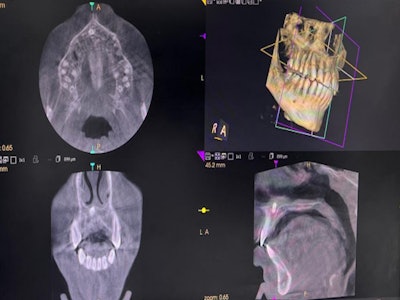

A healthy 13-year-old boy was consulted for preorthodontic surgical removal of an asymptomatic mesiodens in the nasal area. A CBCT scan and orthopantomogram showed that the extra tooth was located submucosally and breaching the nasal floor. Additionally, it was posterior to the boy’s upper right central incisor, the authors wrote.

A CBCT scan shows the teen’s nasally impacted tooth.Images courtesy of Tsakiris et al. Licensed by CC BY 4.0.